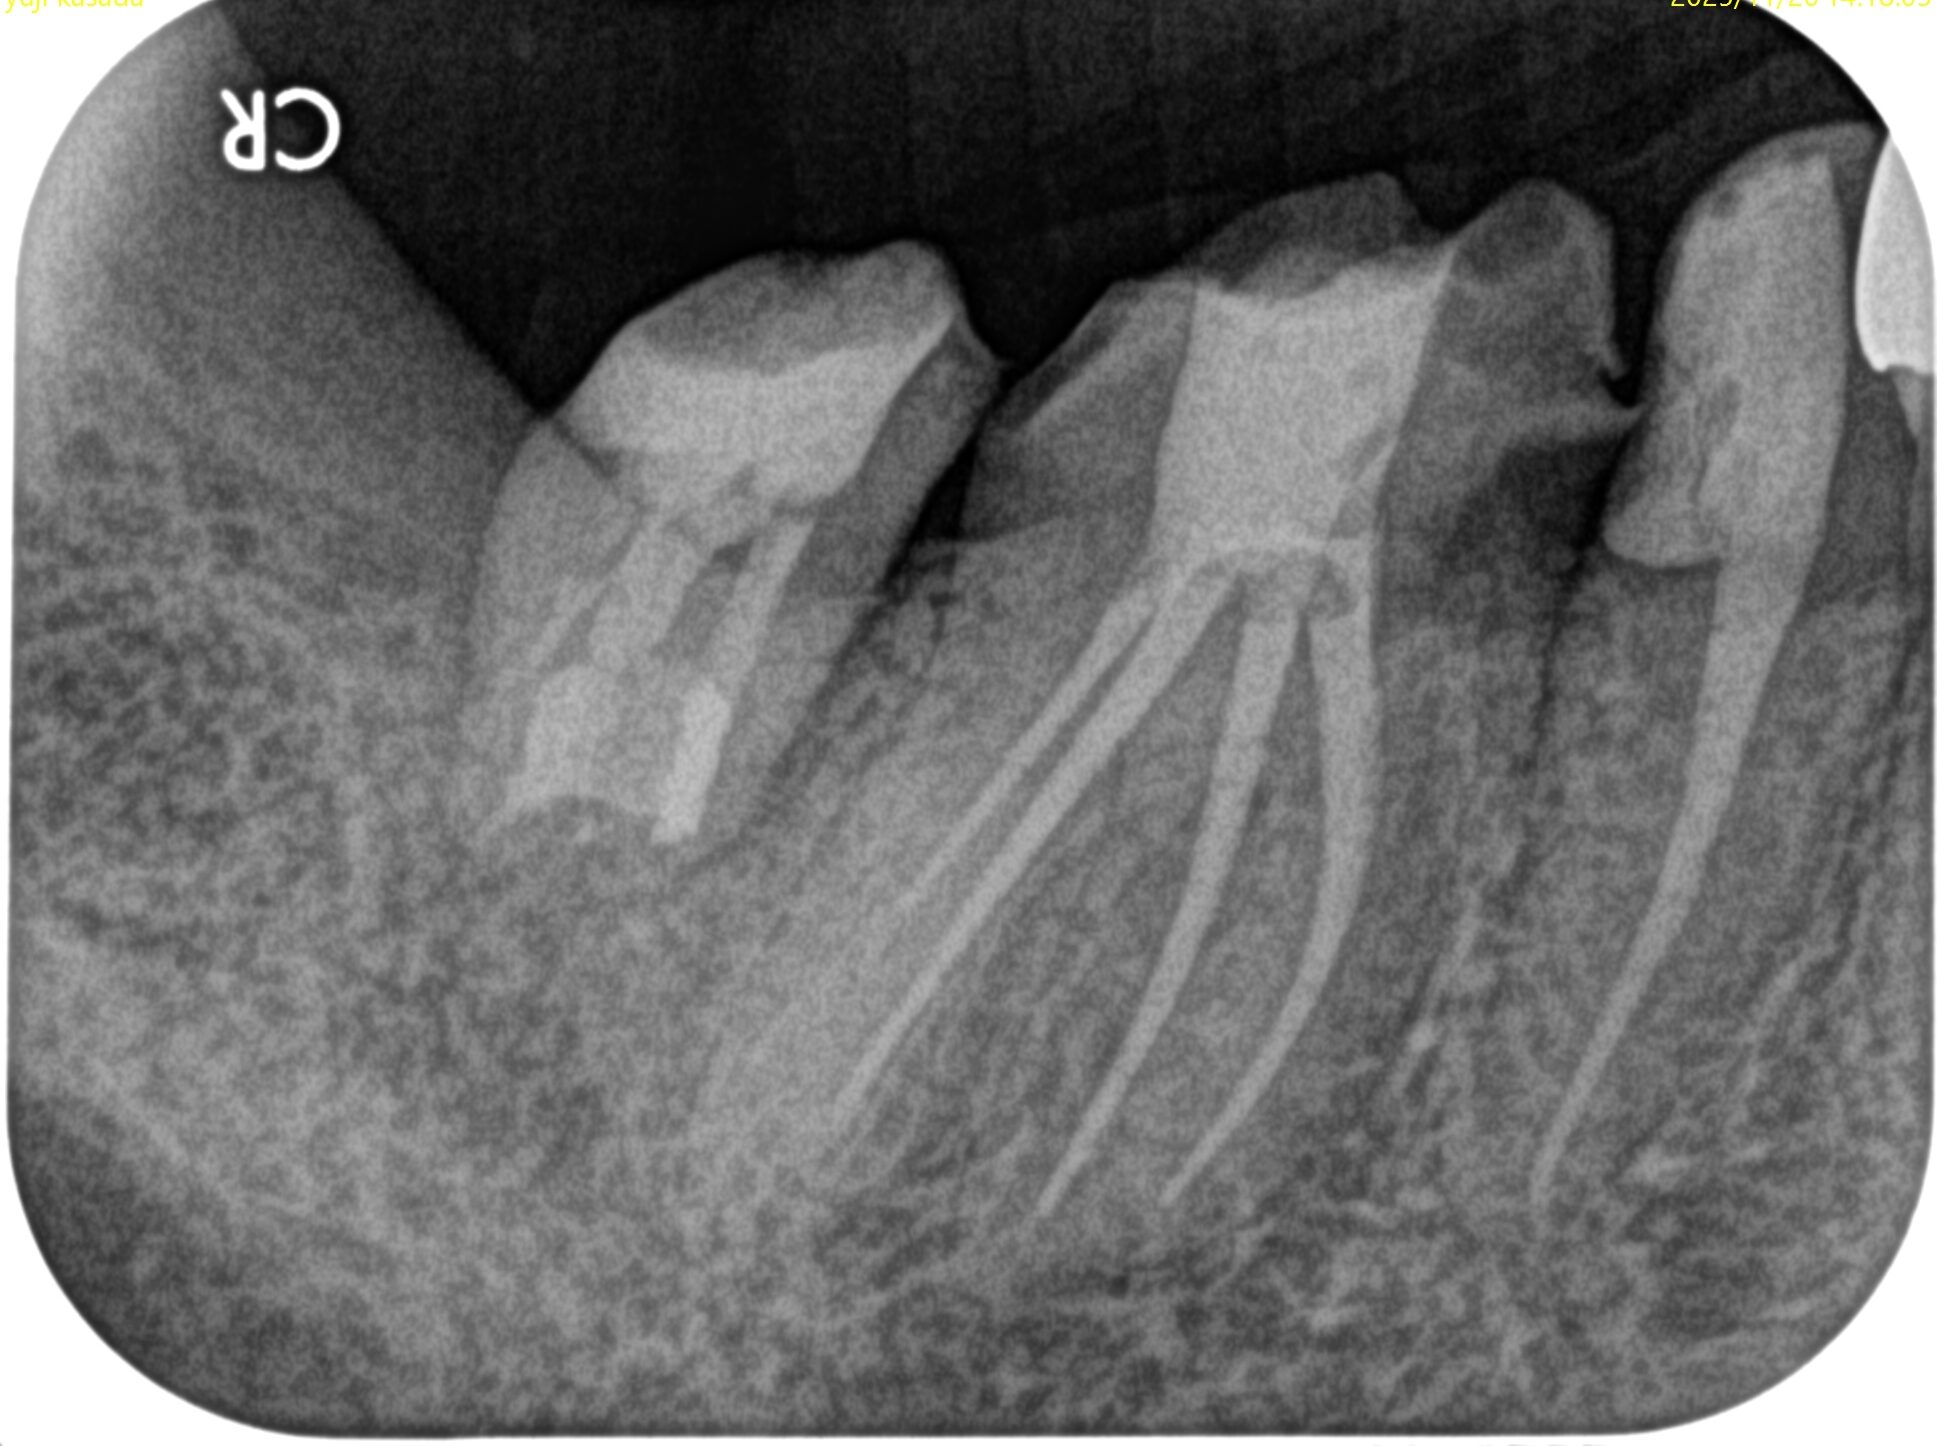

PA(2025.5.19)

確かに…

折れていると言われかねない状況だ。

初診時と比較した。

初診時の絶望的な状況から改善されている。